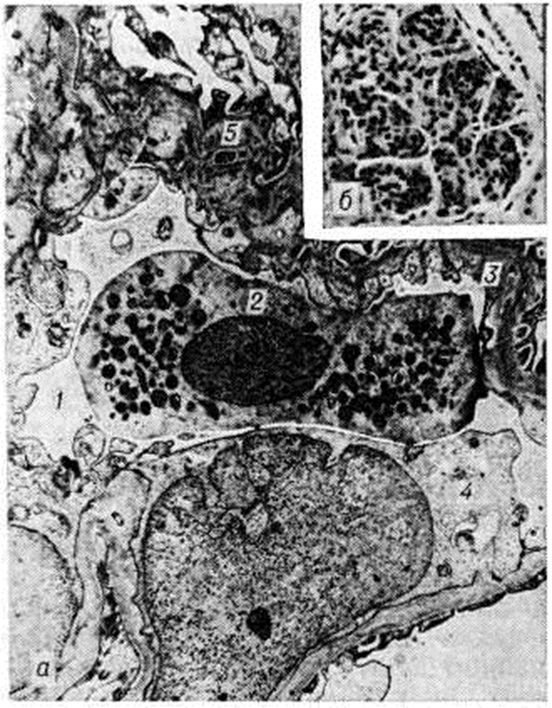

Рис. 1.

Микропрепараты (а, в) и электронограмма (б) почки при мембранозном гломерулонефрите: а—фиксация 131Jγ-глобулина иммунных комплексов на базальной мембране клубочка (прямой метод Кунса); б — мембранозная трансформация, утолщение базальной мембраны (I) гломерулярного фильтра в области субэпителиальных отложений (депозитов) (2) иммунных комплексов, базальная мембрана спаяна с малыми отростками (4) подоцита (3), эндотелий (5) вакуолизирован; ×13 500; в — клубочек при мембранозном гломерулонефрите (окраска гематоксилин-эозином); ×200.

Исходным моментом в повреждении базальной мембраны капилляров клубочков считают фиксацию на ней аутологичных иммунных комплексов (рисунок 1 а), что доказывается методами иммуногистохимии (на базальных мембранах выявляются иммуноглобулины и комплемент) и электронной микроскопии (выявление депозитов на эпителиальной стороне мембраны). При мембранозном Гломерулонефрит, обозначаемом как диффузная мембранозная гломерулопатия (перимембранозный, или экстрамембранозный, Гломерулонефрит, липоидный нефроз взрослых), на наружной стороне базальной мембраны появляются гранулярные депозиты (рисунок 1 б) иммунных комплексов и отложения плазменных белков, тогда как внутренняя сторона мембраны имеет обычные контуры. Депозиты отделены друг от друга выступами lamina densa, направленными в сторону эпителия, в результате чего мембрана имеет вид гребня (мембранозная трансформация по Чергу). В результате «вымывания» депозитов базальная мембрана становится неравномерной плотности. Со временем между депозитами и ножками подоцитов образуются перемычки, они сливаются и уплотняются. Мембрана утолщается за счёт новообразованного слоя кнаружи от депозитов, которые инкорпорируются, подвергаются резорбции и становятся менее осмиофильными. При выраженных мембранозных изменениях пролиферация клеток клубочка отсутствует.